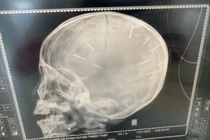

Ông nội bé 3 tuổi nghi bị bạo hành: "Tôi mong cháu vượt sống làm người, đời không thể ngắn ngủi được" - Ảnh 5.

Hình ảnh chụp X-quang hộp sọ của bệnh nhi. Ảnh: Đ.X.

Theo ông Kiên, Bệnh viện Đa khoa Xanh Pôn đã tiến hành chụp cắt lớp dựng hình, nhận thấy có những hình ảnh giống những đinh gỗ ở sọ và tổ chức não, tổng cộng 9 cái.